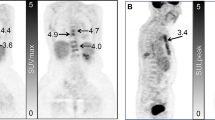

Up to five of the most active (SUV ≥ 10) [23] and largest (≥ 1 cm diameter) lesions were first identified for analysis on [18F]fluoride scans in each subject. Regions of interest (ROIs) were delineated around the same metastasis on the static [18F]fluoride and [18F]FDG PET/CT scans by an oncologist and radiologist working in consensus (Figs. 1 and 2). Image heterogeneity analysis was performed using in-house quantitative analysis software implemented in MATLAB (Mathworks, Natick, MA, USA). First-order statistics derived from regional geometry and the histogram distribution of voxel intensities (standard deviation (SD), entropy, uniformity, kurtosis and skewness) on both [18F]FDG and [18F]fluoride PET scans were calculated as well as non-heterogeneity parameters such as SUVmax, SUVmean, SUVpeak, TLM and MTV. All parameters on both PET scans were calculated for the same lesions at baseline and 8 weeks, and changes in the values of these parameters from baseline were used for statistical analyses. The tumour volumes were generally small ((mean volume = 7.1 cm3 (SD = 8.3) on [18F]fluoride PET/CT and (mean volume = 5.7 cm3 (SD = 5.9) on [18F]FDG PET/CT)); therefore, in order to avoid bias from small volumes, second and high-order texture features were not calculated [24, 25]. We also analysed changes in SUVmax between lesions in each individual patient to assess the degree of interlesional heterogeneity of response with both tracers. Interlesional heterogeneity was defined when a metastasis showed a change in parameter that was opposite to the clinical reference standard.

Figure demonstrating regions of interest in L4 in a patient with non-progressive disease (partial response). a, c [18F]FDG and b, d [18F]fluoride PET transaxial slices a, b before and c, d 8 weeks after treatment. [18F]FDG SUVmax 8.4 at baseline and 4.4 at 8 weeks. [18F]fluoride SUVmax 72.1 at baseline and 46.5 at 8 weeks.